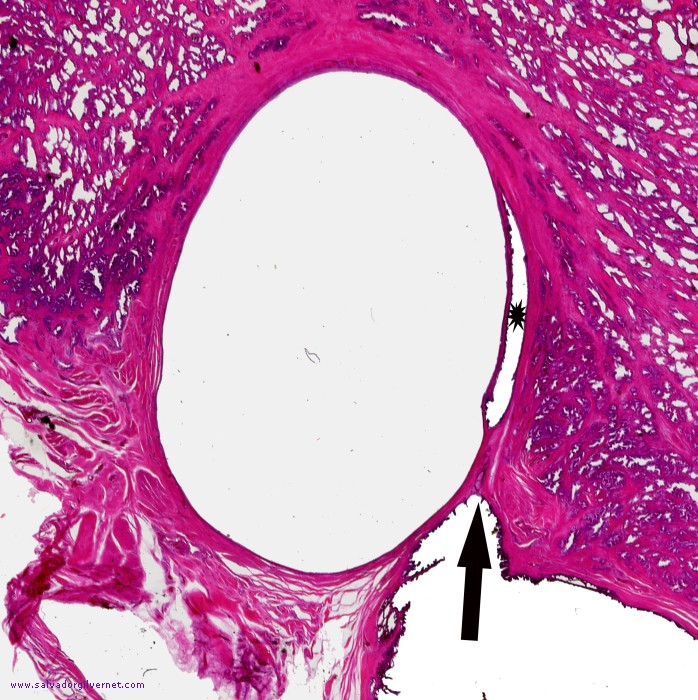

Detalle 1: Porción proximal del conducto eyaculador derecho dilatada (flecha) y porción intraprostática del conducto eyaculador (asterisco) comprimida por el quiste utricular

• Sección frontal oblicua que interesa la porción proximal del conducto eyaculador derecho, ampolla deferencial y vesícula seminal derecha. Quiste de utrículo y porción proximal del conducto eyaculador, ampolla deferencial y vesícula seminal muy dilatados (Detalle 1)